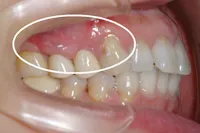

術後1ヶ月

術前に比べ、歯茎の組織が再生され、健康な状態の時とほぼ同様になりました。